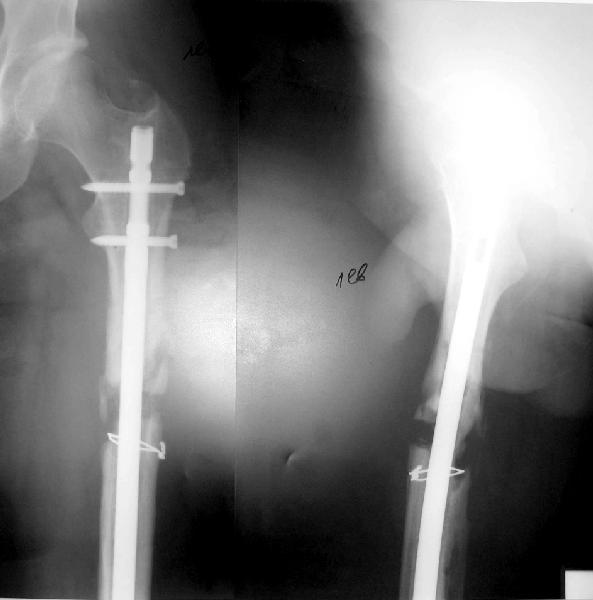

фото несращения бедра

Имя     : фото 5.jpe

Имя     : фото 4.jpe